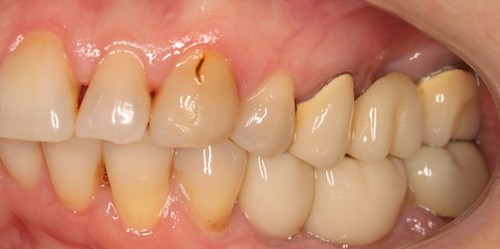

До